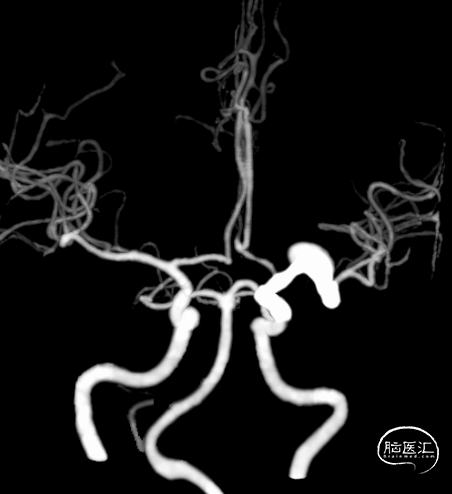

题目:左侧大脑中动脉M1段夹层动脉瘤FD植入术

Title:Flow Diverter (FD) implantation for a dissecting aneurysm at the M1 segment of the left middle cerebral artery

摘要:47岁中年女性,因头部外伤后发现颅内动脉瘤4个月入院。诊断:左侧大脑中动脉M1段夹层动脉瘤。经过术前充分抗血小板药物治疗后,首先球囊扩张夹层近端的狭窄,然后植入血流导向装置覆盖整个血管夹层,术中发现支架打开不良,给予支架内球囊扩张及微导丝按摩处理后最终支架完全打开,夹层段血管得到修复,围手术期未出现神经缺损,术后5个月随访,mRS评分为0分。

Abstract:A 47-year-old female was admitted for the treatment of an intracranial aneurysm found 4 months following a head trauma. The diagnosis confirmed a dissecting aneurysm at the M1 segment of the left middle cerebral artery. After preoperative antiplatelet therapy, a flow-diverting device was deployed following balloon angioplasty of the dissection's proximal stenosis. Intraoperative stent misdeployment was corrected with additional balloon dilation and micro-guide wire manipulation, leading to full stent expansion and vascular reconstruction. No neurological deficits occurred perioperatively. At the five-month follow-up, her modified Rankin Scale (mRS) score was 0, indicating a complete recovery.

2024年4月1日 DSA

L ICA

Pre-OP

Post-OP